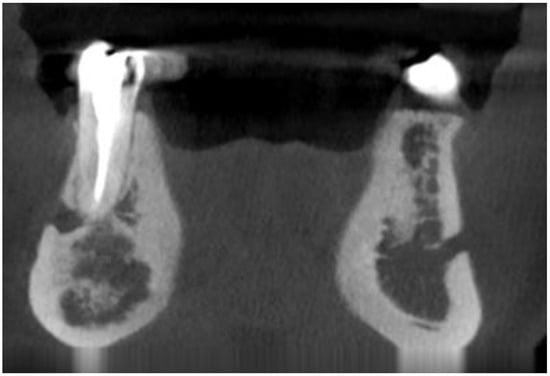

- various stages of calcifying masses inside of the lesion, Figure 5

- may cause cortical expansion or teeth displacement, Figure 5.